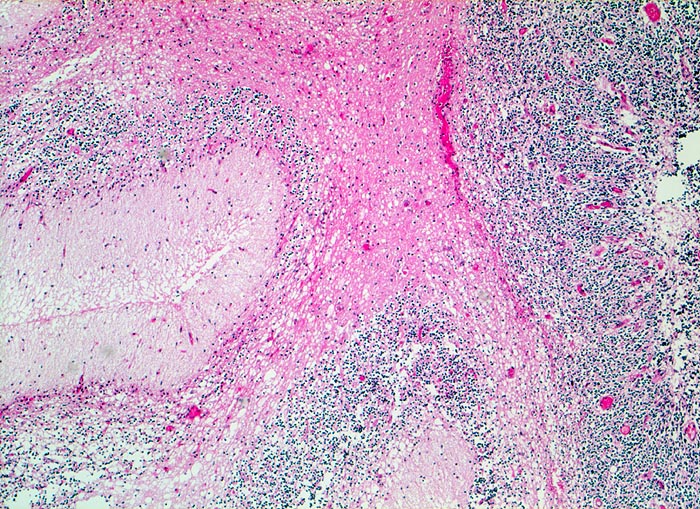

• Scharf begrenzter rundlicher sehr zellreicher (deshalb blauer) Tumor.

Wegen der hohen Zelldichte und der hohen Kern-Zytoplasmarelation erscheinen die Tumoren in der HE Färbung blau. Medulloblastome müssen differentialdiagnostisch von morphologisch ähnlichen kleinzelligen undifferenzierten Karzinomen und Lymphomen abgegrenzt werden. Das klassische Medulloblastom besteht aus dicht gepackten Zellen mit runden bis ovalen oder karottenförmigen stark hyperchromatischen Kernen umgeben von wenig Zytoplasma. Runde Zellen mit weniger dichtem Chromatin sind oft beigemischt. Zahlreiche Mitosen, flächenhafte Nekrosen und Apoptosen sind typisch. In weniger als einem Drittel der Fälle findet man die typischen Homer-Wright Rosetten. Diese bestehen aus ringförmig angeordneten Tumorzellkernen um ein fibrilläres Zentrum aus Zytoplasmafortsätzen.